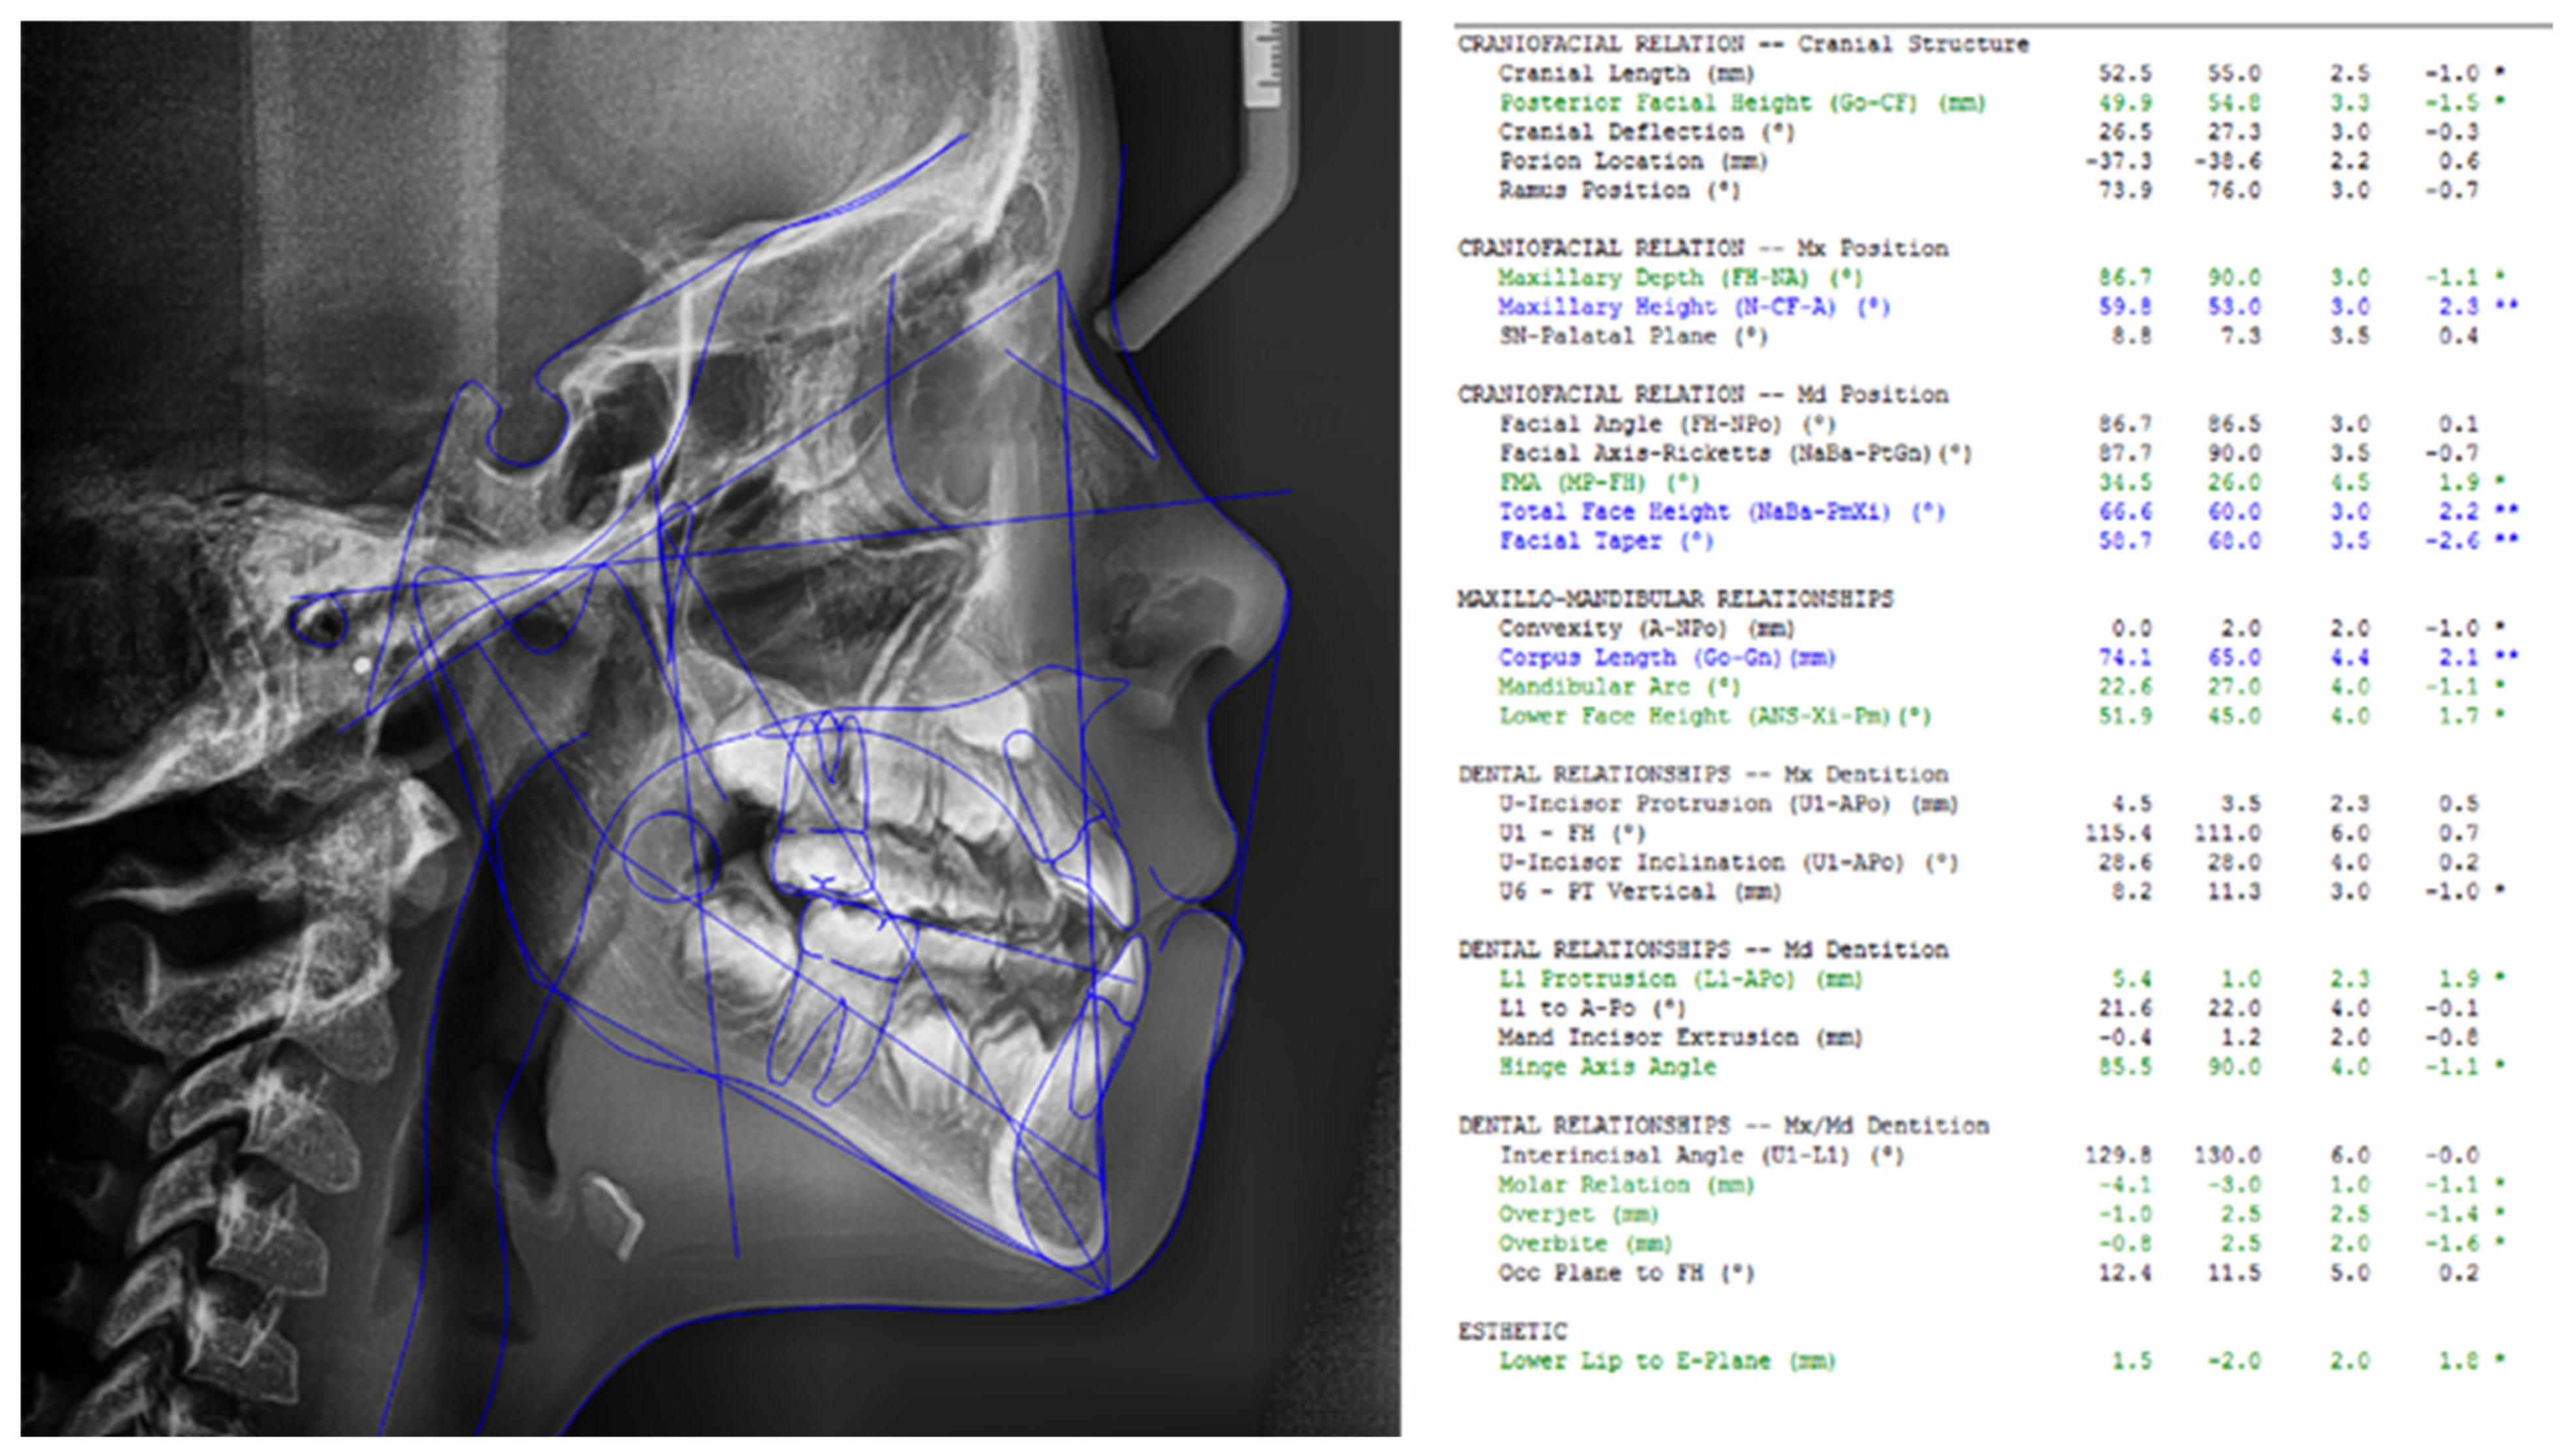

We analyzed the following individual cephalometric parameters to define the facial growth pattern: SN-GoGn (Sella–nasion to gonion–gnathion angle), XY (the angle between the Ricketts facial axis and the NBa line), Facial Axis, Mandibular Plane, Facial Depth, Facial Cone, Maxillary Height, Maxillary Deflection, Posterior Facial Height and Lower Facial Height (Figure 1). No significant differences were detected between groups for any of the parameters (Table 4).

Figure 1.

Ricketts cephalometric tracing with cephalometric values defining the facial growth pattern. * Slight deviation from the standard values; ** Moderate deviation from the standard values.